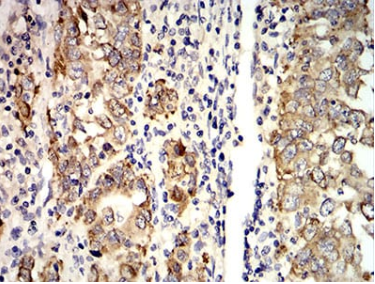

AGR2 Mouse Monoclonal antibody[5G1F8]

AGR2 (Anterior Gradient 2, Protein Disulphide Isomerase Family Member) is a Protein Coding gene. Diseases associated with AGR2 include pancreatic ductal adenocarcinoma. Among its related pathways are Tyrosine Kinases / Adaptors and Adhesion. GO annotations related to this gene include dystroglycan binding. An important paralog of this gene is TXNDC12.

Immunogen:   Purified recombinant fragment of human AGR2 (AA: 21-175) expressed in E. Coli.

IHC    1/200 - 1/1000